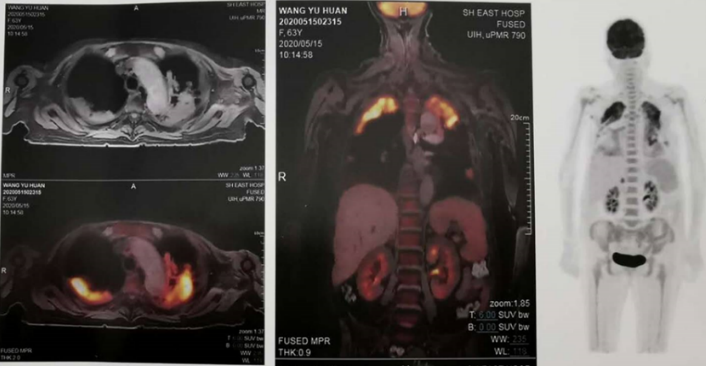

图片

患者,女性,63岁,因“干咳、心慌、呼吸困难2个月,渐加重”收住RICU;间断发热、半年内体重下降20 kg。外院诊断“重症肺炎,肺结核”,行抗感染、抗结核治疗,病情加重。患者因“心房纤颤”服用胺碘酮治疗,半年内胺碘酮累积剂量达189.4 g,后因全身不适自行停药。

急诊血气分析:pH 7.28,PaO2 45 mmHg,PaCO2 62 mmHg;SaO2 83%,HCO3- 23 mmol/L,SBE 1.3 mmol/L。

血常规:WBC 26.5×109/L,NEU% 95%,Hb 85.0 g/L。

炎性标志物:CRP>150.00 mg/L(↑),SAA>320.00 mg/L(↑),ESR 91 mm/h(↑),IL-6 505 pg/ml(↑),PCsT 0.232 ng/ml(↑)。

心肌酶、心功能:pro-BNP 9024 ng/L(↑),CK-MB 1.610 ng/ml,TNT 0.057 ng/ml(↑)。

肝功能:AST 173 U/L(↑),ALT 376 U/L(↑),LDH 1124 U/L(↑),Y-GT 3502 U/L(↑),白蛋白28 g/L(↓)。

血肿瘤标志物:CA19-9 33.40 U/ml(↑), CA125 230.00 U/ml(↑),铁蛋白2711.00 ng/ml(↑)。

甲状腺功能:TT3 0.72 ng/ml(↓),TT4 20.20 μg/dl(↑),FT3 1.56 pg/ml(↓),FT4 2.13 ng/dl(↑),TSH 10.200 μIU/ml(↑),TAb 18.20 ng/ml。

胸部CT:双肺多发中高密度炎性病灶,双上肺为著。部分肺组织受压不张,双侧胸腔积液;纵隔见多发肿大淋巴结;心脏增大,心包积液(图3

图3  患者入院时胸部CT

拟诊:脓毒症,多脏器功能不全,肿瘤不除外。给予高流量呼吸支持,胸腔穿刺+持续闭式引流,抗感染,脏器保护+营养支持治疗,同时行BALF、胸水、外周血标本的传统病原学检查(涂片,培养,PCR,抗原,抗体)结果均阴性;外周血结缔组织病、血管炎相关疾病阴性;血及胸腔积液肿瘤标志物中仅CA125、CA199轻度升高;胸腔积液+BALF脱落细胞学阴性。

PET-CT:双肺多发实变影及斑片影,FDG代谢异常增高;结合病史,考虑双肺炎性病变;纵隔淋巴结炎性增生,双侧胸腔积液;肝脏弥漫性异常信号改变,FDG代谢减低,考虑弥漫损伤性改变;右侧肾上腺结节,FDG代谢轻度增高,考虑良性病变,腺瘤可能;双肾小囊肿4)

4  患者全身PET-CT